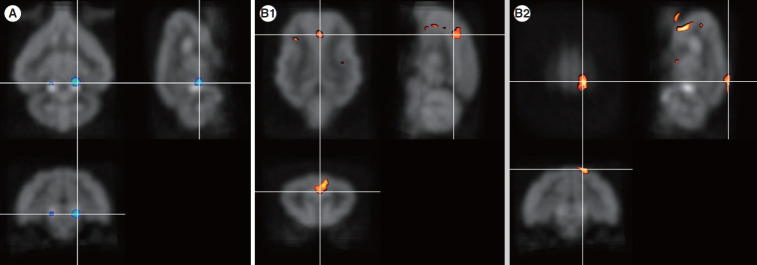

Results: Four months after hearing loss, the auditory cortical area's activity decreased, and activity in the associated visual area increased. After 7 months of cochlear stimulation, the superior marginal gyrus and cingulate gyrus, which are components of the default mode network, showed hypermetabolism. The inferior colliculi showed hypometabolism.

Conclusion: Resting-state cortical activity in the default mode network components was elevated after cochlear stimulation. This suggests that the animals' awareness level was elevated after hearing restoration by the cochlear implantation.